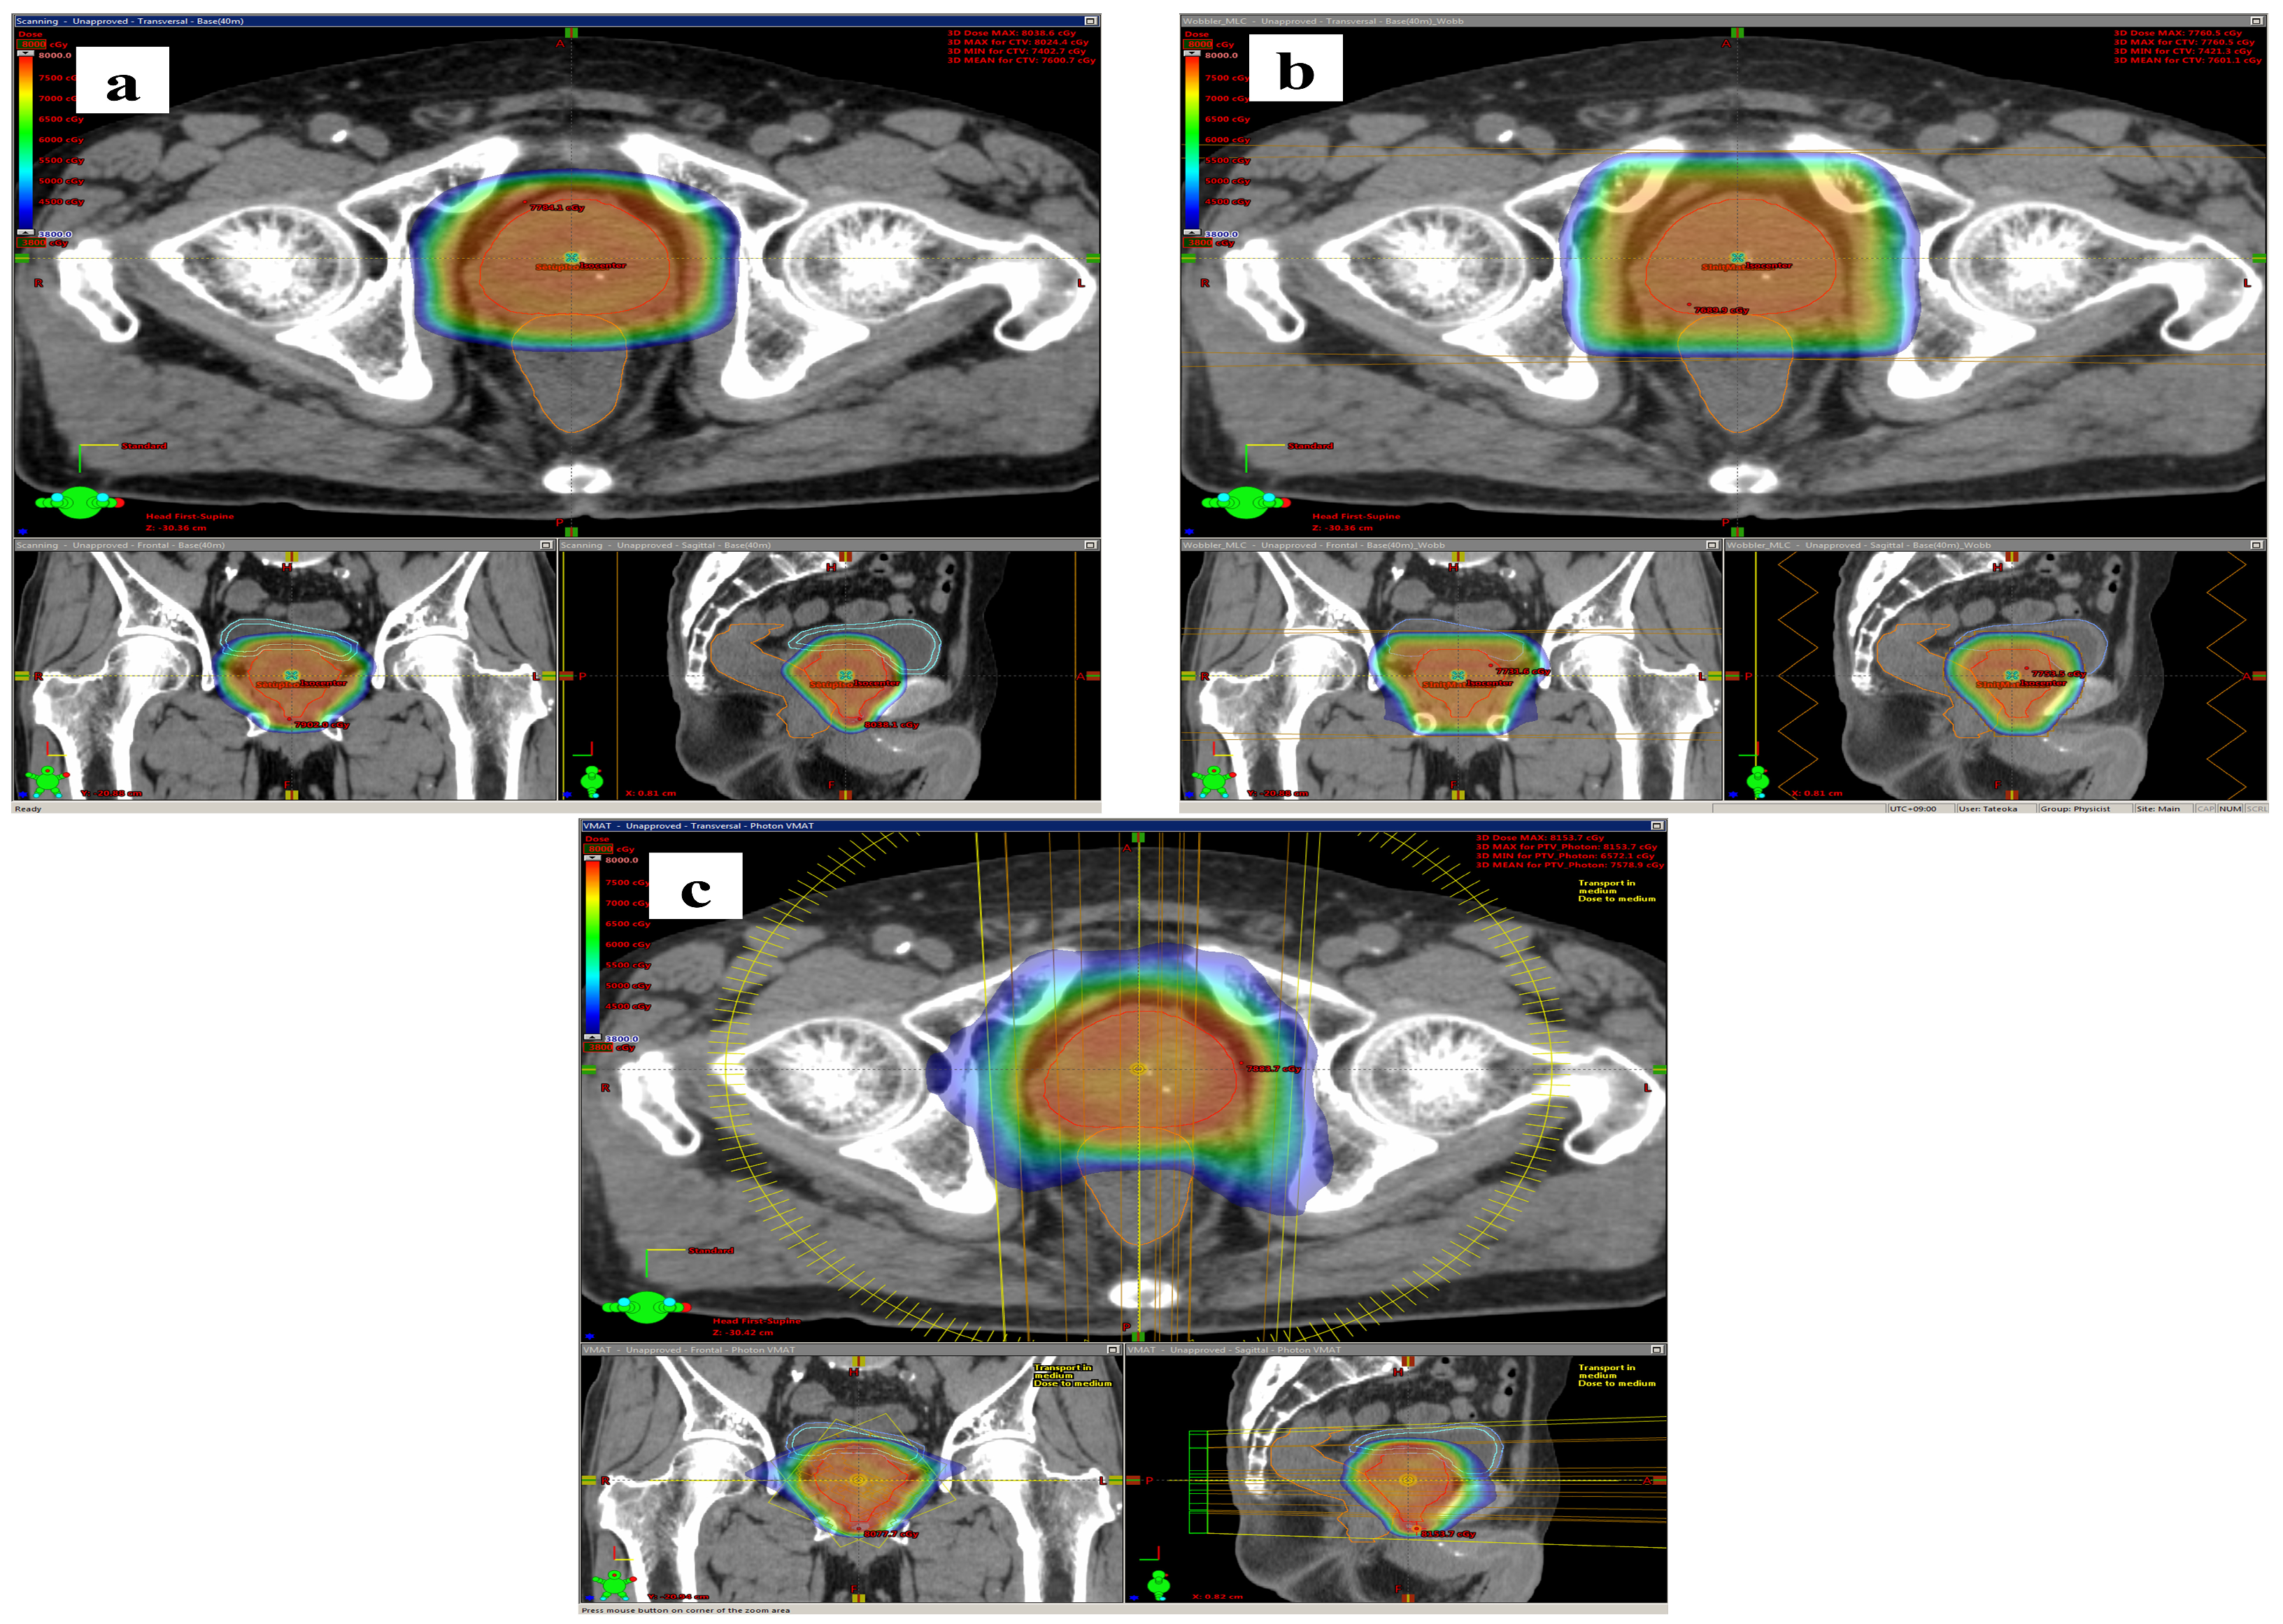

2.4.1. LS Method

2.4.2. PS Method

2.4.3. VMAT